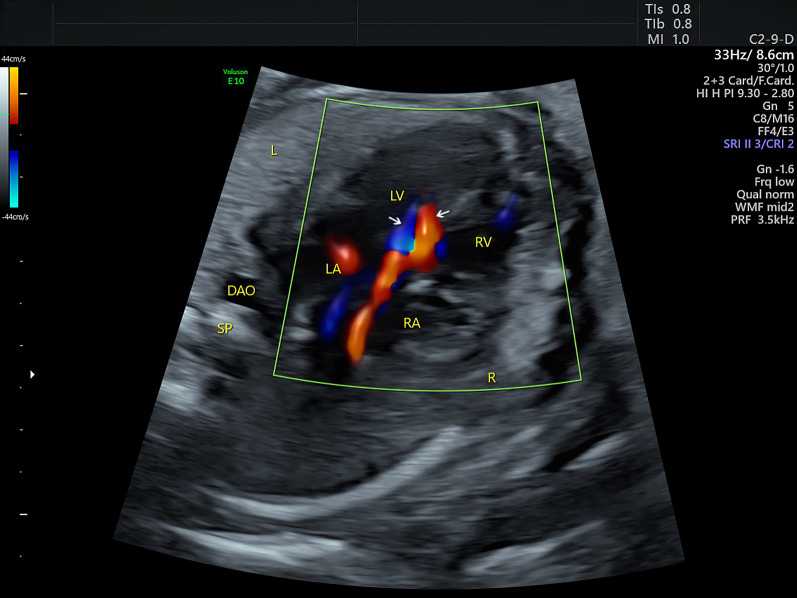

Fig. 1.

Sonograms of the fetus of coarctation of the aorta at the four-chamber view. The four-chamber view shows symmetrical left and right chambers. In addition, a bidirectional shunt (indicated by the arrows) between the left and right ventricles is demonstrated by color Doppler. DA: ductus arteriosus; DAO: descending aorta; L: left; LA: left atrium; LV: left ventricle; R: right; RA: right atrium; RV: right ventricle; SP: spine

A 32-year-old woman, gravida 3, para 1, was referred to our center at 26 + 3 weeks of gestation for further fetal cardiac examination for suspected cardiac anomalies. The patient was in good health without any maternal complications or high-risk factors (e.g. diabetes, hypertension, amniotic disorders). A detailed echocardiogram was performed to find any potential cardiac anomalies using transverse and sagittal scanning. Conventional 2DE was used to show fetal anatomical structures. Color Doppler flow imaging (CDFI), together with HDFI was used to show fetal hemodynamics. The sound beam was continuously moved upward along the vertical axis of the fetal thorax to perform the transverse scanning. The four-chamber view (4CV) showed a symmetrical left and right heart. The left and right outflow tract views showed normal ventriculoarterial connections. However, a small-sized ventricular septal defect (VSD) was identified at the 4CV and the left outflow tract view with the communication clearly shown by CDFI (Fig. 1). An additional movie file shows this in more detail (See Additional file 1: Video). The pulmonary valve annulus (PVA) was apparently wider in comparison with the aortic valve annulus (AVA). The ratio of PVA/AVA was 1.6 in diameter. The size of the pulmonary artery (PA) was also larger than the aorta (AO) and the ratio of PA/AO was 2.1 in diameter. At the three-vessel trachea (3VT) view, the widened pulmonary trunk continued to be the ductus, which was connected with the descending aorta. At the same time, a tiny vessel was found located at the right side of the pulmonary trunk, with no convergence with the ductus (Fig. 2). An additional movie file shows this in more detail (See Additional file 2: Video). Under normal conditions, the aortic arch joins with the ductus to form proximal descending aorta in a characteristic “V” shape at the 3VT view [2]. The echocardiographic manifestations in the current case thus suggest the possibility of an IAA. Sagittal planes were also scanned to obtain more information. The arch did not present, instead, the ascending aorta was visualized going straight upward and then branching three brachiocephalic arteries in a “W” shape (Fig. 3). An additional movie file shows this in more detail (See Additional file 3: Video). A preliminary diagnosis of IAA type A was then reached. The 3DE with STIC technology was then used to obtain 3D images of the great arteries to confirm the 2D diagnosis. A 3D motorized transducer (4–8 MHz) was used to acquire cardiac volumes when scanning the sagittal planes using HDFI. The acquisition time was set to 12.5 s and the sweep angle was set to 30°. Cardiac volumes were acquired automatically and then reconstructed to display in a cine loop in multiplanar mode. Volume post-analysis was then performed using an off-line software (4D viewer, version 14.0) to obtain the 3D reconstructed images. This could be achieved by properly adjusting the direction and size of the region of interest (ROI) and the rotation of the images in three orthogonal planes in the volume. A combination of smooth surface and gradient light algorithms was also used to enhance the 3D effect of the reconstructed images. The 3D image demonstrated an abnormal angle of attachment of the aortic arch to the ductus and descending aorta via a slim isthmus (Fig. 4). An additional movie file shows this in more detail (See Additional file 4: Video). The final diagnosis was CoA at the isthmus.